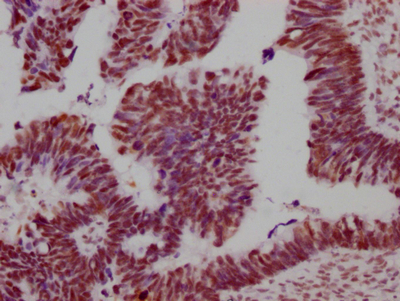

IHC image of CSB-RA149196A0HU diluted at 1:100 and staining in paraffin-embedded human ovarian cancer performed on a Leica BondTM system. After dewaxing and hydration, antigen retrieval was mediated by high pressure in a citrate buffer (pH 6.0). Section was blocked with 10% normal goat serum 30min at RT. Then primary antibody (1% BSA) was incubated at 4℃ overnight. The primary is detected by a Goat anti-rabbit IgG polymer labeled by HRP and visualized using 0.05% DAB.